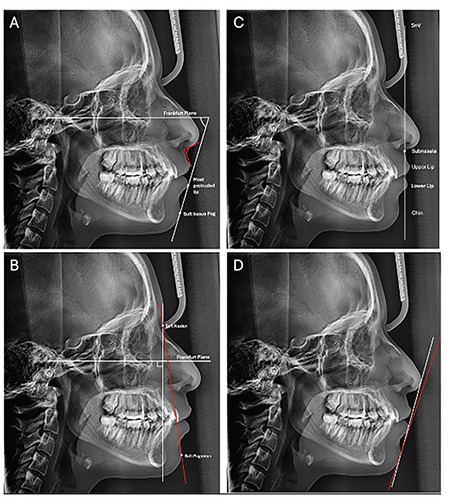

Objective: To compare soft tissue profile variations between Class I and Class II adult patients due to three vertical skeletal facial patterns (normodivergent, hypodivergent and hyperdivergent) and determine which skeletal variation has the most significant impact on soft tissue profile.

Methods: Retrospective soft tissue profile analysis was performed on lateral cephalograms of 131 adult patients. The analysis was divided into two categories correlated with subnasal and general soft tissue profiles. The sample was divided based on two sagittal skeletal patterns (Class I and II) and three vertical groups. In addition, comparisons were made between males and females. Viewbox 4 was used for the analysis. Descriptive, comparative, and correlation statistics were performed using SPSS software.